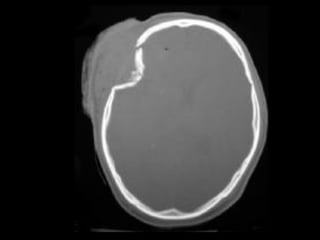

Os plats

Crâne

boîte contenant l’encéphale,

formée de :

Base

Voûte

•La base du crâne

•La voûte du crâne